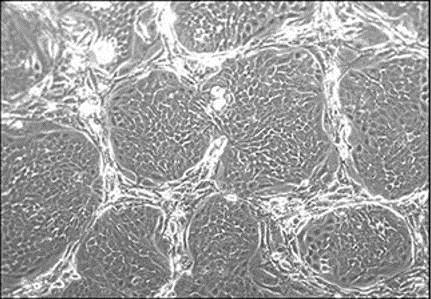

在饲喂细胞层上生长的肿瘤上皮细胞